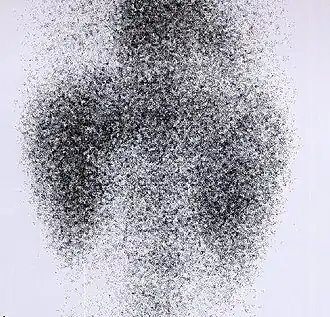

DMSA scan

Decreased Tc99m-DMSA uptake in both kidneys, suggestive of renal failure.